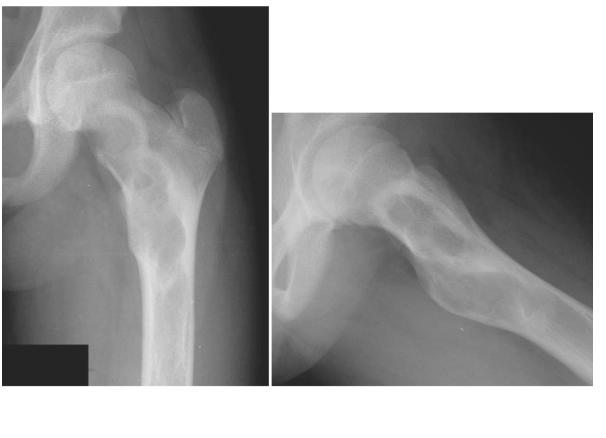

KONDROSARKOM

Doktor Mehmet Subaşı

Sıklıkla 40-60 yaş arası görülür.erkeklerde kadınlara ora...